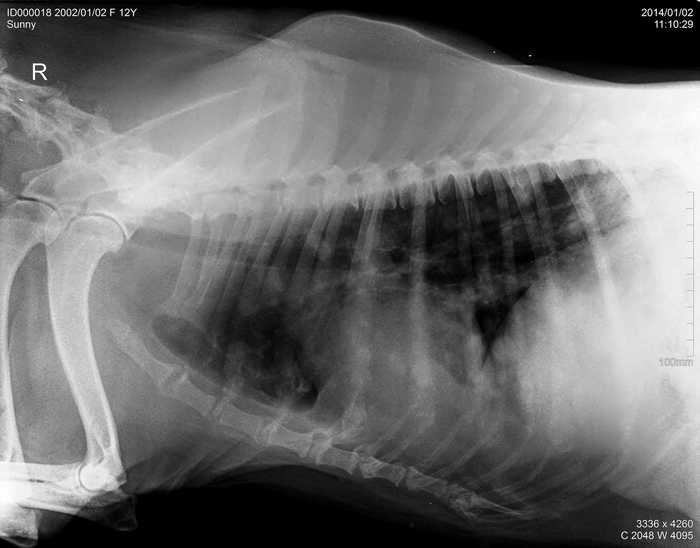

Úvod > Galerie > RTG snímky